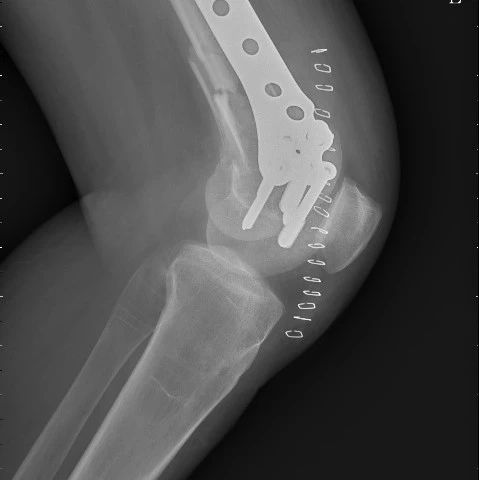

(股骨骨折术后)